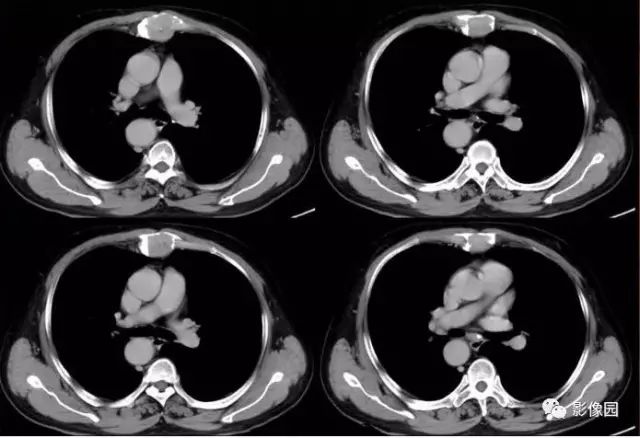

肚肚丫头: 胸骨体局部呈膨胀性骨质吸收破坏,内呈软组织密度影,可见点状钙化,增强扫描呈轻度强化,周围软组织略肿胀。考虑:1.骨巨细胞瘤;2.浆细胞瘤;3.嗜酸性肉芽肿

CT表现:特征性穿凿状、鼠咬状及蜂窝状骨破坏,边缘清楚,骨质疏松,病理性骨折及软组织肿块等表现,骨质硬化及骨膜反应少见。

骨破坏区完全为软组织取代,骨质膨胀,边界清楚,常突破骨皮质形成软组织肿块。增强扫描可见病灶轻中度强化,一般于静脉期达峰值。